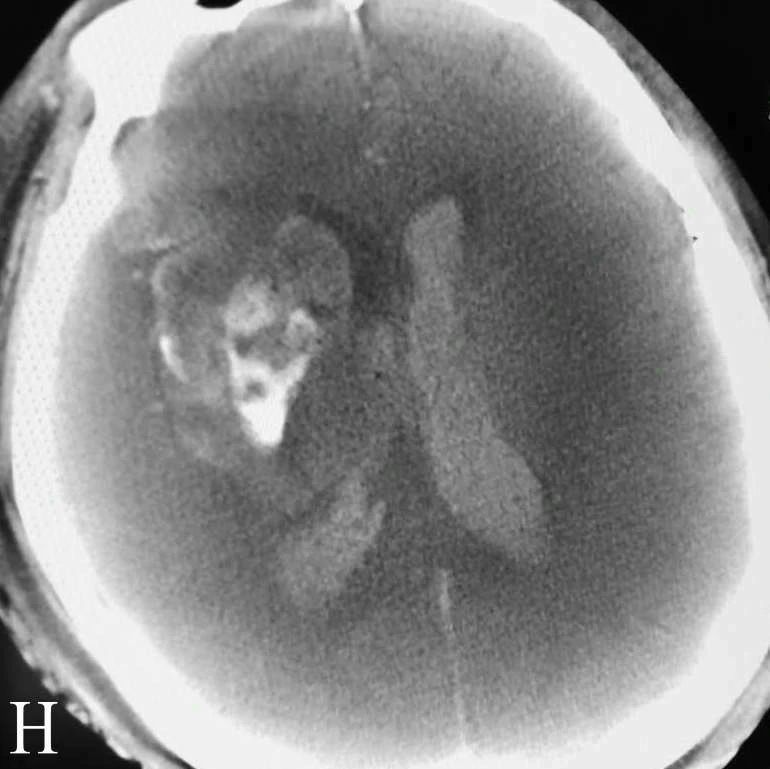

H:术后即刻DynaCT示再灌注出血

患者急诊行介入取栓治疗,术中发现双侧股动脉均未触及搏动,穿刺异常困难,最后在超声引导下行右侧股动脉高位穿刺获得成功。造影发现右侧颈内动脉分叉部T型闭塞,球囊导引导管辅助下支架取栓开通闭塞血管。取栓术后行腹主动脉造影发现腹主动脉下段闭塞,考虑亦为心源性栓塞,血管外科行股动脉切开取栓,取出大量血栓。患者术后CT提示右侧半球再灌注出血,2天后脑疝死亡。